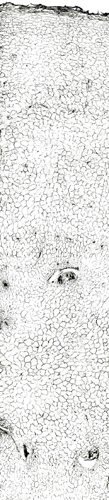

内部形態:鏡検

本品はほぼ偏球形を呈し、径1~2cmで、一端に茎の跡がある。外面は灰黄色~灰褐色で質は堅く、破砕面は黄色で平滑または灰黄緑色で粒状である。 本品はほとんどにおいがなく、味は苦い。 Corydalis属は、39節、約428種が広く世界に分布するといわれ、このうち38節,約288種が中国に分布している。このうち塊茎をつくるものは4節であり、分布が局地に限られるものを除くと、Sect. Duplotuberと Sect. Pes-gallinaceus の2つの節に限られる。Sect. Duplotuber にはチョウセンエンゴサク C. ternata (Nakai) Nakai (C. nakaii Ishidoya) および、ジロボウエンゴサク C. decumbens (Thunb.) Persが含まれる。Sect. Pesgallinaceusには C. yanhusuo Wang ex Su et Wu (C. turtschaninovii Besser forma yanhusuo Y. H. Chou et C. C. Hsu)が含まれるとされている。 |

内部形態の比較(市場品)

浙江省産市場品の横切面では、形成層は明瞭で環状につながっている。道管は形成層の近くに散在しており、中央に髄がある。コルク層を表面視するとコルク細胞は厚膜の長条形である。 韓国産市場品の横切面では、維管束が放射状に配列し、形成層は不明瞭で放射組織によって分断され、環状につながらない。コルク層を表面視すると、コルク細胞は薄膜の多角形である。

| ○延胡索 甲級 <中国浙江省> |

○延胡索 乙級 <中国浙江省>・上部 |

○延胡索 <韓国> |

兵庫県柏原における試験栽培品(浙江省産を種付け)は浙江省市場品と同様の形態を呈していた。 <横切面> ・形成層は明瞭で環状につながる。 ・道管は形成層の近くに散在している。 ・中央に髄がある。